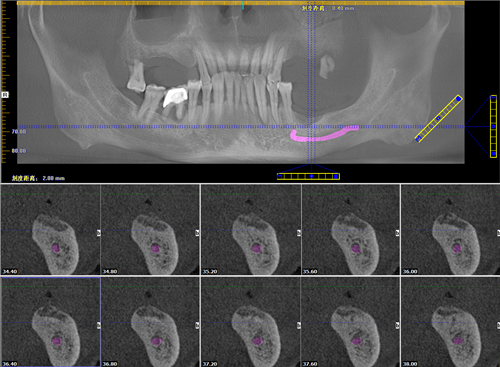

郭老牙齿全景片

通过一系列的检查后,麦芽口腔郑苍尚院长为他量身定制了"微创无痛数字化口腔种植牙"技术,舒适的种牙体验,就像被蚊子"叮"了一下牙就种好了,用郭老的话说:"种牙过程很轻松,全程无痛,种完后也不肿不痛的,相信麦芽就是相信科学"。